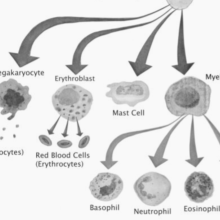

Diabetes: how could stem cells help?

Cord blood stem cells: current uses and future challenges